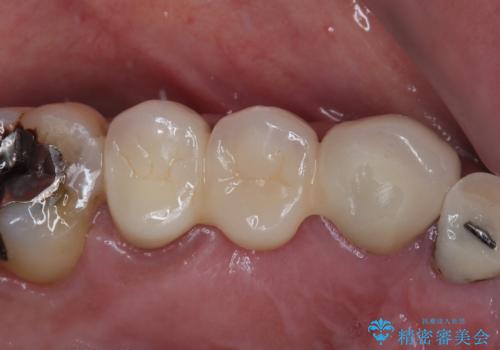

破折した歯 オールセラミックブリッジの補綴治療

咬合力が強く、抜歯となる破折歯の前後の歯はいずれも神経が除去された歯であることから、ブリッジでは長期的な予後に不安があると判断されましたが、前後の銀歯も一気にきれいにしたいとのことで、オールセラミックブリッジによる補綴治療を行うこととしました。

ブリッジの支台が破折した場合にはインプラント治療が必須となるため、咬合力による破折を避ける目的で、就寝時のマウスピース装着が非常に重要となります。